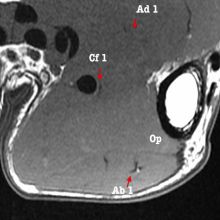

Elle est constituée de quatre muscles, cités de la profondeur à la superficie :

- le muscle adducteur du pouce, innervé par le nerf ulnaire, permettant l'adduction du pouce ;

- le muscle court fléchisseur du pouce, innervé dans sa partie superficielle par le nerf médian et dans sa partie profonde par le nerf ulnaire, permettant la flexion et l'adduction du pouce ;

- le muscle opposant du pouce, innervé par le nerf médian, amenant le pouce en opposition des autres doigts ;

- le muscle court abducteur du pouce, innervé par le nerf médian, permettant l'abduction et la rotation médiale du pouce.